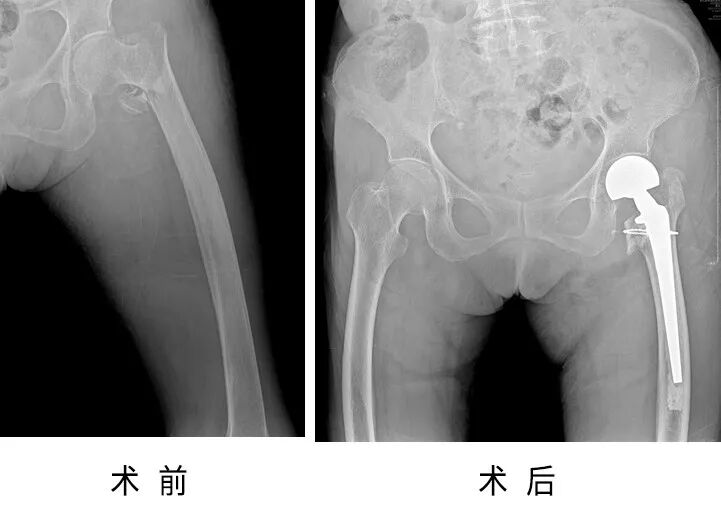

患者楊奶奶,85歲,因走路不慎摔倒,導(dǎo)致左髖腫痛、畸形,疼痛難忍,不能站立及行走。

家人帶著楊奶奶求診于省級(jí)知名骨科專家、邦爾骨科集團(tuán)首席專家、嘉興邦爾骨科醫(yī)院院長(zhǎng)趙凱教授,診斷很明確——“左側(cè)股骨粗隆間骨折”,需要盡快進(jìn)行手術(shù)。在對(duì)患者進(jìn)行充分的術(shù)前評(píng)估后,趙凱教授帶領(lǐng)四肢關(guān)節(jié)組團(tuán)隊(duì)為楊奶奶順利完成了“左側(cè)人工股骨頭置換術(shù)”。

手術(shù)從麻醉到結(jié)束,僅用一個(gè)小時(shí)左右的時(shí)間,創(chuàng)傷小、時(shí)間短、出血量少。術(shù)后一周,楊奶奶可以在家屬幫助下,扶著助步器行走。

術(shù)前術(shù)后對(duì)比圖

75歲的李爺爺,6年前出現(xiàn)左側(cè)髖部疼痛,近年來疼痛癥狀逐漸加重,嚴(yán)重影響生活。

經(jīng)人介紹,李爺爺找到了省級(jí)知名骨科專家、邦爾骨科集團(tuán)首席專家、嘉興邦爾骨科醫(yī)院院長(zhǎng)趙凱教授,診斷為“左側(cè)股骨頭無菌性壞死”。趙凱教授帶領(lǐng)四肢關(guān)節(jié)組團(tuán)隊(duì),為李爺爺順利完成了“左側(cè)人工全髖關(guān)節(jié)置換術(shù)”。

術(shù)后3天,李爺爺已經(jīng)可以在康復(fù)師協(xié)助下,利用助行器行走,術(shù)后半個(gè)月,李爺爺已經(jīng)可以正常行走。